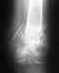

Re: Остеосинтез большеберцовой кости голени.Не выкручивается шуруп?

Снимки покажите.